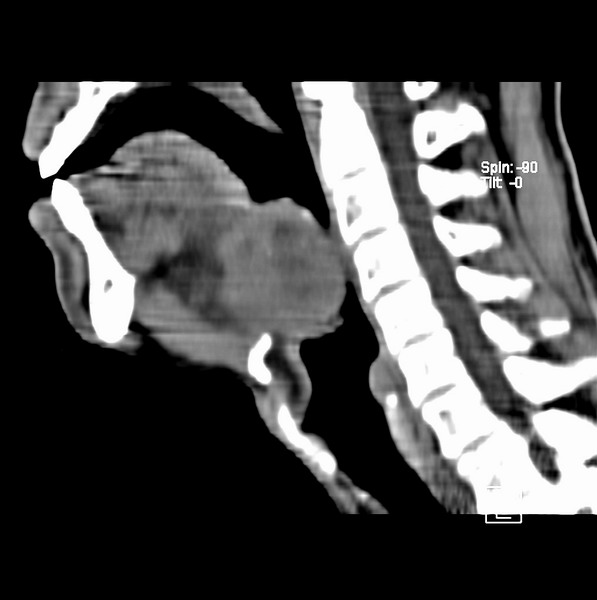

标题: CT19620:舌根肿物

男、60、舌根肿物。

舌垂直肌和横肌影处肿块影,边缘不规则,咽腭扁桃体及舌下间隙脂肪影消失,病变侵及口咽。

考虑-----舌根癌

舌跟软组织肿块,较大有坏死,钙化。结合年龄一般是恶性肿瘤。

舌根部较大软组织肿块,其内见坏死低密度区及钙化影;考虑舌根癌可能。

支持考虑舌根癌或会厌癌